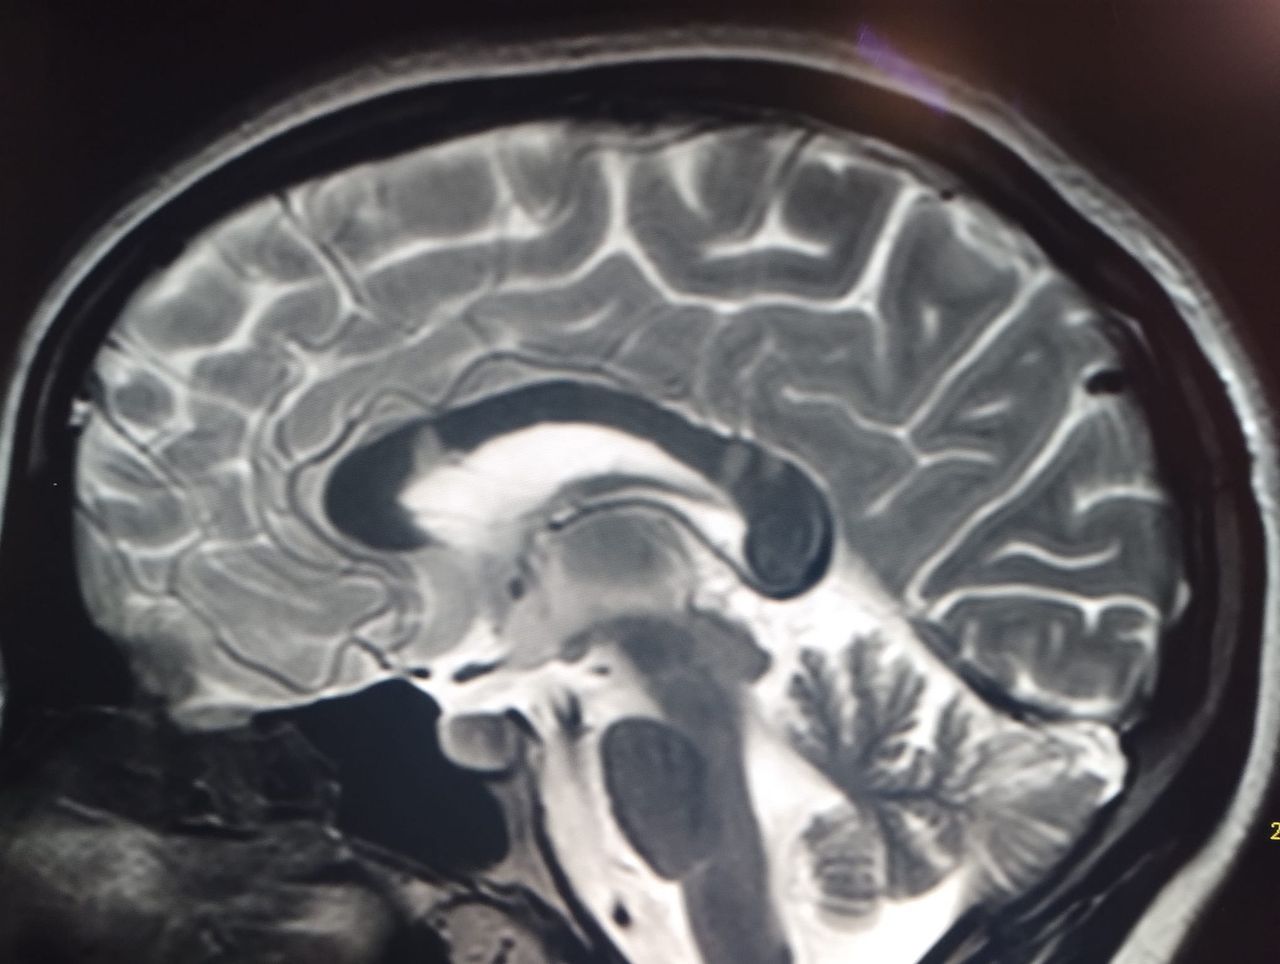

Foto e video

• Risonanza magnetica

150 €

• Ospedale G. Di Maria, Avola (Sr) Risonanza Magnetica Encefalo e tronco encefalico  •